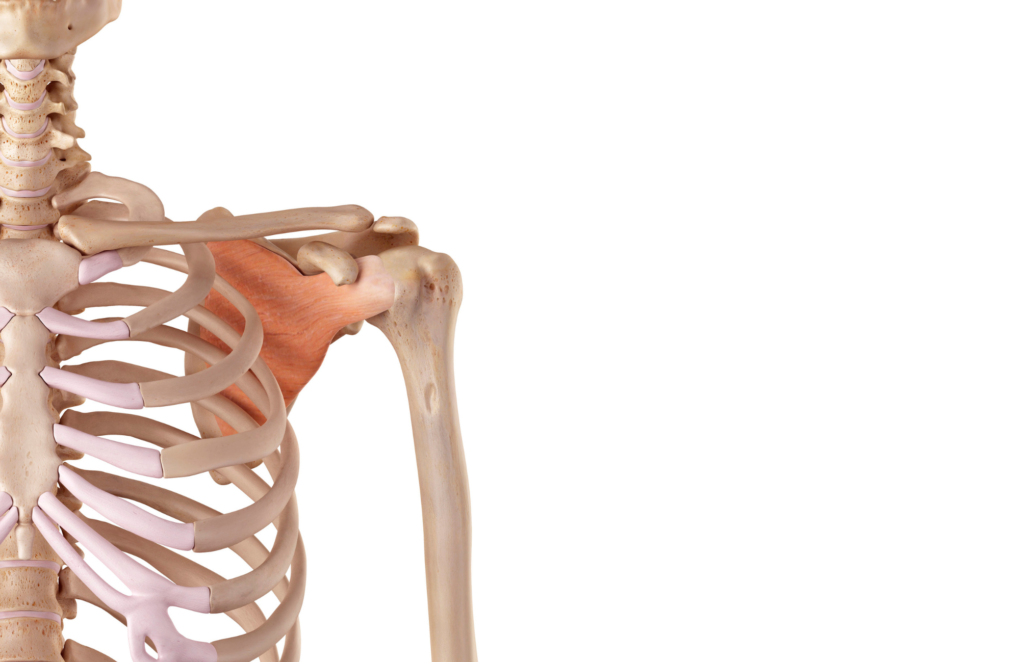

Anatomia del Muscolo Sottoscapolare

Il sottoscapolare è un muscolo triangolare che si trova sulla superficie anteriore della scapola, occupando l’intera fossa sottoscapolare. Origina dalle superfici interne della scapola e si inserisce sul tubercolo minore dell’omero. Questo muscolo è unico tra i muscoli della cuffia dei rotatori in quanto è l’unico ad agire sulla rotazione interna del braccio. Il suo tendine si fonde con la capsula articolare della spalla, contribuendo significativamente alla stabilità dell’articolazione.